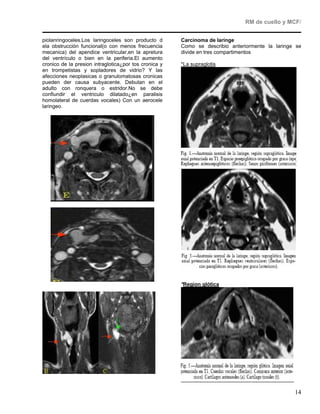

Espacio parafaríngeo

Axial supresión grasa

Contenido                                            Patología

Quiste del segundo arco

Grasa

branquial

Peligro por

MTTS/abscesos

Diseminacion

Quiste del segundo arco branquial

El quiste branquial es una patología relativamente

común, de etiología discutida; por ello se han

descrito varias teorías para intentar explicar la

aparición de estos quistes. La primera, la más

aceptada por la mayoría de los autores, explica su

existencia como derivados del aparato branquial

(Hosemann y Wigand, 1988); el aparato branquial

se desarrolla de la tercera a la séptima semanas

del crecimiento fetal y consiste en seis pares de

Coronal supresión grasa

arcos       mesodérmicos         separa-dos        por

invaginaciones de endodermo por la zona interna y

Absceso parafaringeos

ectodermo por la externa (bolsas branquiales). Los

Lesión ocupante mal definida, que tiene un centro

quistes y fístulas son el resultado de la falta de                                           licuado y neurótico y paredes que refuerzan.

cierre o resolución de éstos, siendo más frecuentes

Cuando el absceso se extiende de lado a lado

las de segundo arco debido a que es el que                                                   puede tener el aspecto de moño

persiste más tiempo en el desarrollo embrio-

lógico9. La segunda teoría trata de relacionar la

aparición de estos quistes con procesos de

amigdalitis y faringitis; así el epitelio escamoso

derivado de la faringe llega a la vía linfática, a los

ganglios linfáticos regionales y el crecimiento en

ellos de este epitelio desarrolla el quiste3.Existe

una tercera teoría que determina el posible origen

de estos quistes al tejido parotídeo basándose en

el hallazgo de tejido parotídeo glandular en el

interior de los quistes extirpados.A veces se

considera lesión del espacio parotídeo